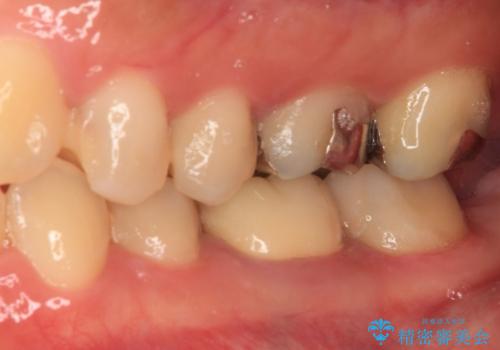

- 処置が必要と言われていたものの、長い間放置していた奥歯の治療を希望して来院された患者様です。

一番奥の歯は詰め物が脱離しており、仮詰め材が詰まっており、手前の歯は根管治療後に樹脂で固めたままの状態でした。

手前の歯を仮歯に置き換えるとともに、一番奥の歯のむし歯治療を行うこととしました。